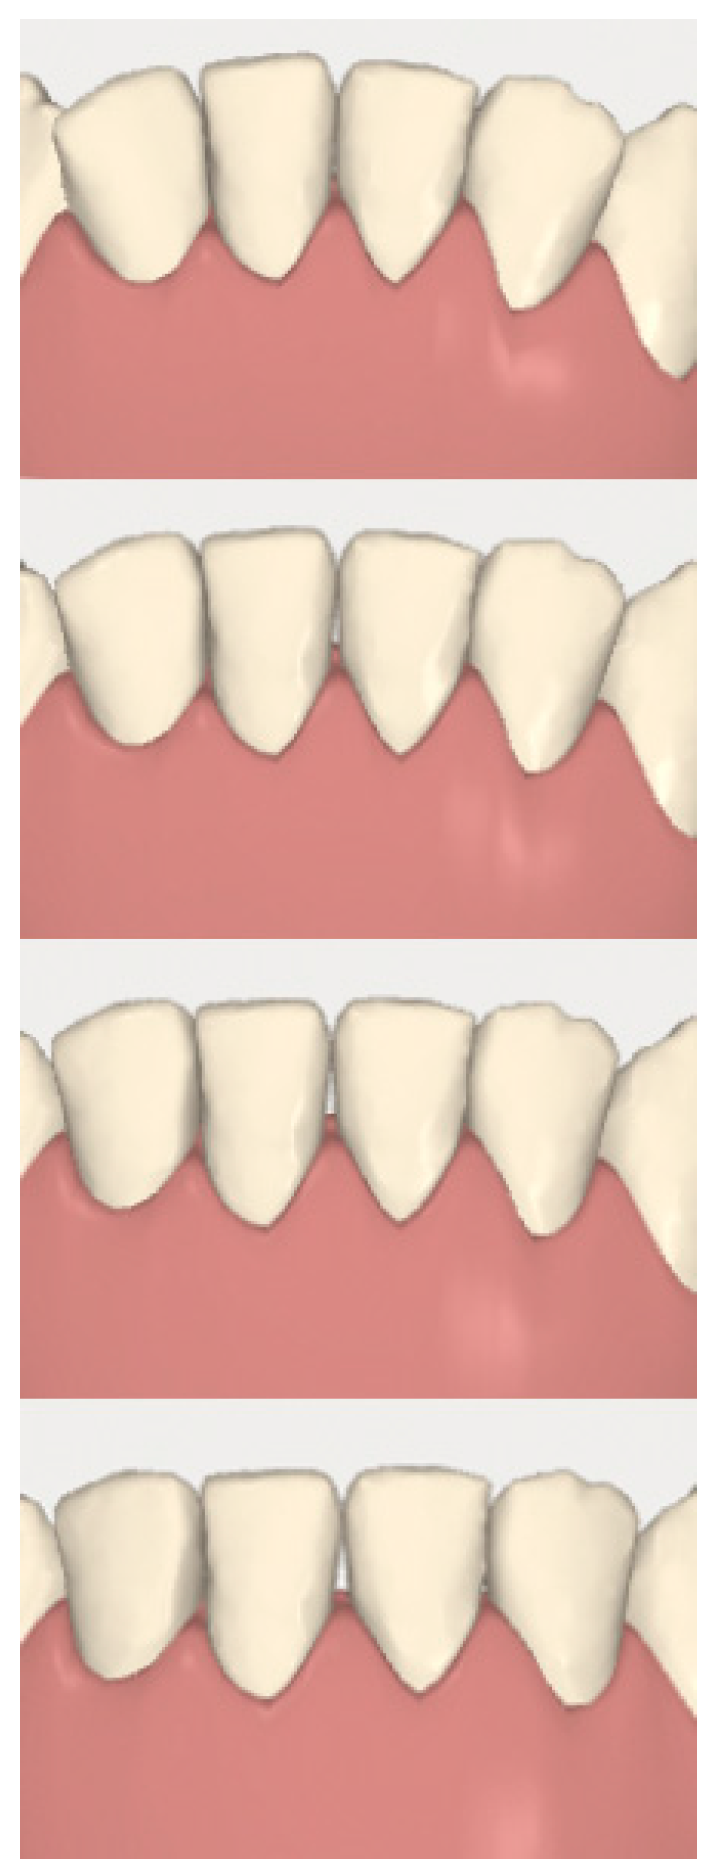

2.2. Orthodontic Planning

2.3.1. Example—Anterior Open-bite

2.3.2. Example 2—Extraction Space Closure